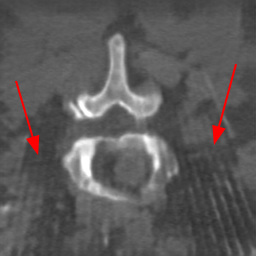

Disentanglement and explicit shape constraints. As shown in Fig. 4, we can see streak metal artifacts nearly everywhere in . M1 can roughly disentangle artifacts and anatomical information but strong vertical artifacts and strange air area appear in (see red arrows of M1 in Fig. 4). For the anatomical structure, M1 learns to segment vertebrae with fully supervised and applied on various CT images, but fails to suppress the false bony structure in and as may misclassify some metal artifacts as bone.

Implicit shape constraints. With , all segmentations are improved with higher Dices and smaller ASDs, see Table 1. As shown in Fig. 4, , and become similar but the high density bone is not correctly segmented in as it maybe treated as metal artifacts. Comparing between M2 and M1, the abnormal air region disappears but metal artifact reduction performance is still not satisfactory.

Anatomy-aware generation. With AADE layer in M3, , and are substantially improved as shown in Table 1. Note, is used as attention map, so we do not expect it to be identical to . In , metal artifacts are further suppressed comparing with M2. Thus, AADE is critical to our anatomy-aware artifact disentanglement framework. With the special structure, can be punished in the image translation and reconstruction processes and the other encoders and generators receive more guidance. However, as shown by blue arrows in Fig. 4, we observe a shadow of vertebra edge of appears in of M3 and the vertebra boundaries get smoothed out in . It may be because sharp edges are encoded as metal artifacts and forced to be added to by artifact consistency loss .

Removal of . To mitigate vertebrae shadows, we remove . The segmentation performance of most images in M4 gets improved because of better synthetic images. Overall, in M4 yields the best segmentation performance for CBCT images with an average Dice of 0.847 and an average ASD of 1.54 mm. For the synthetic images, M4 generates with the best quality and least metal artifacts among all the models. M4 also outputs without vertebra shadows. The results indicate our shape-aware network could preserve anatomical details and transfer the metal artifacts precisely without .